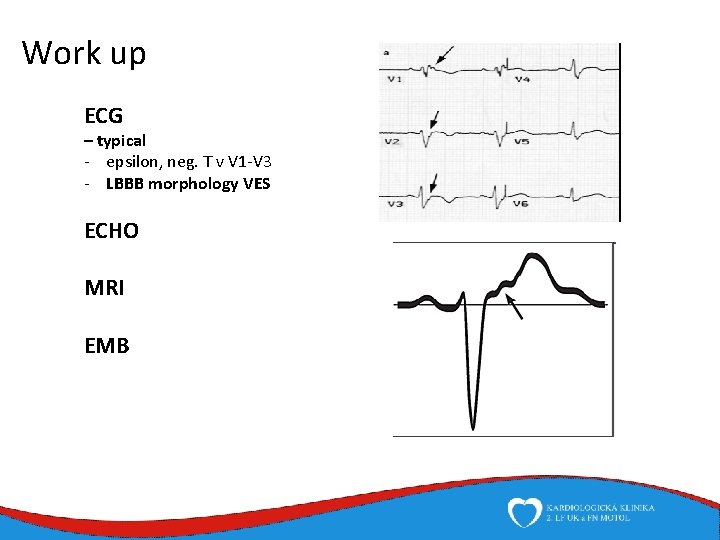

Work up ECG – typical - epsilon, neg. T v V 1 -V 3 - LBBB morphology VES ECHO MRI EMB